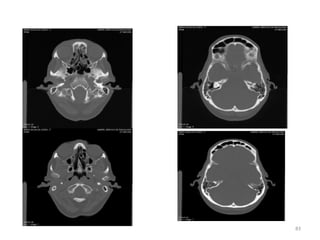

1. Medula espinal

(forame magnum)

2. Células mastóideas.

3. Seio maxilar esq.

4. Côndilo

mandibular(cabeça).

5. Processos zigomáticos.

6. Maxilar.

7. Osso nasal.

1. Cristalino do olho D.

2. Lobo parietal E.

3. Medula Oblonga

(bulbo).

4. Seio esfenoidal.

5. Corpo vítrio (globo

ocular).

6. Hemisfério cerebelar D

1. Músculo reto medial D.

2. Músculo reto lateral E.